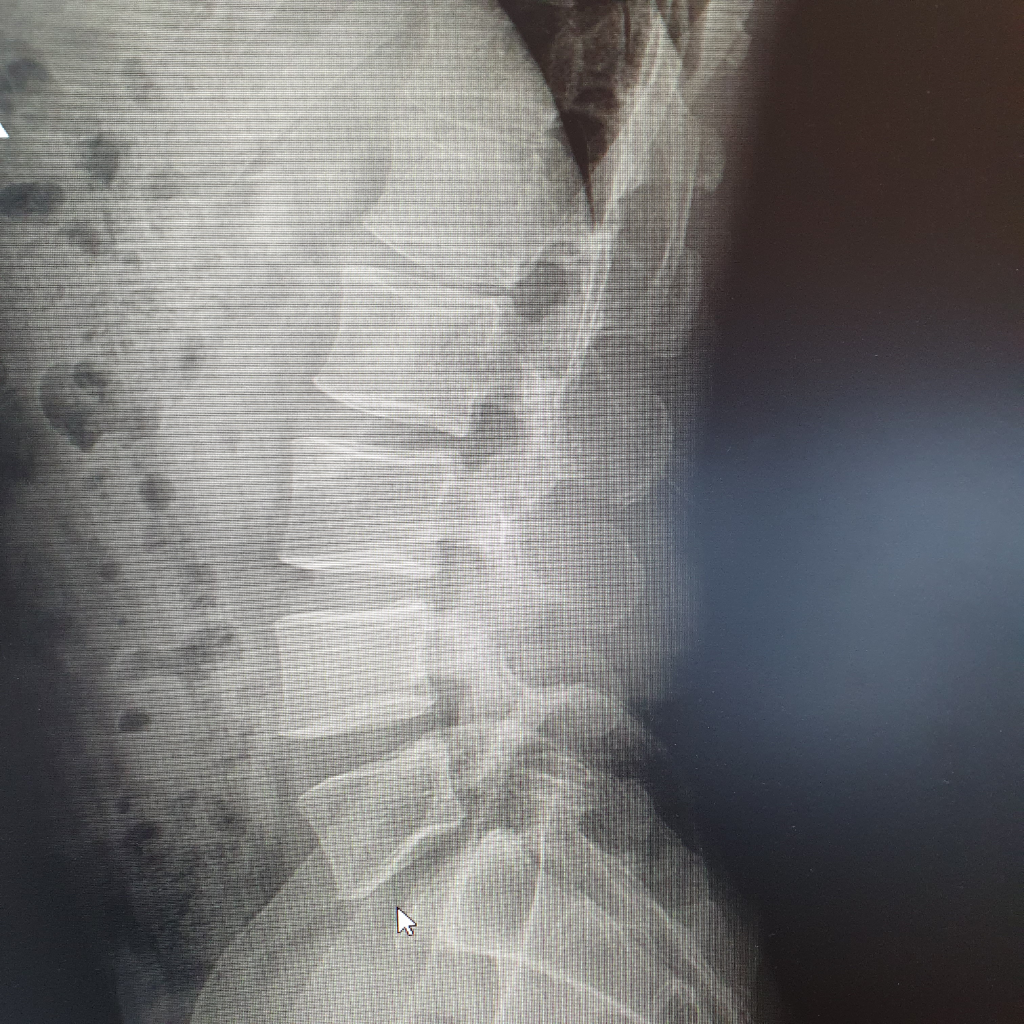

엉치통증으로 정형외과를 갓더니 의사가 엑스레이를 찍어보니 선천적으로 척추분리증으로 인해 엉치신경통이 있는 것이라고 합니다

엑스레이 사진 찍어왓는데 저정도면 많이 심각한 것인가요?

지금도 가볍지만 척추전방전위가 있어보입니다.

천추뼈 위의 요추5번 뼈가 살짝 앞으로 이동해있습니다.